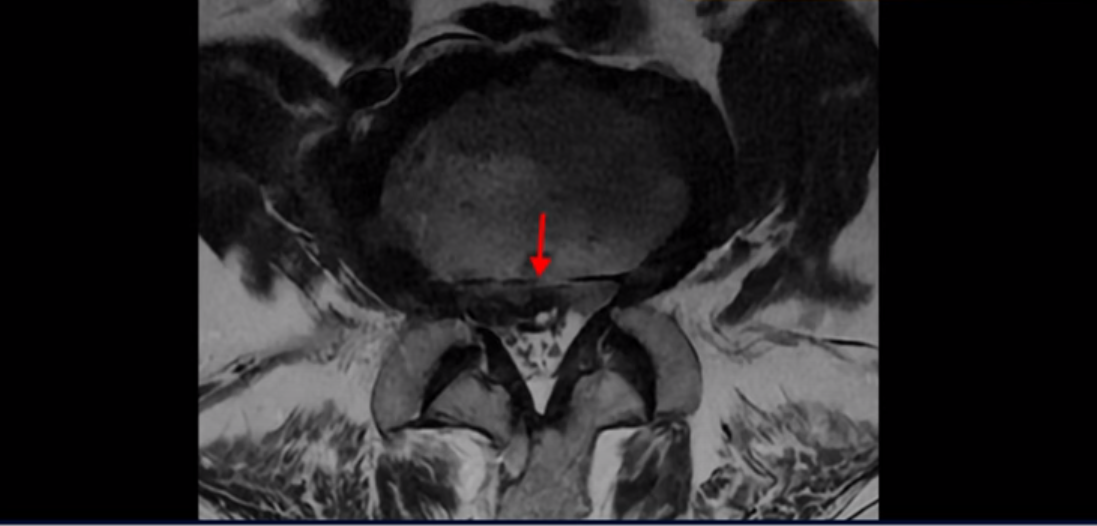

4번 5번에는 척추관협착과 심한 디스크 파열이 있습니다.

기립근의 지방화도 심합니다. 또 3번 4번 마디에서는 신경가지가 빠져나가는 추간공이 왼쪽, 오른쪽 모두 많이 좁아져 있습니다.

이런 이유로 이 환자분은 왼쪽 다리는 마비가 생겨 힘이 빠지고 오른쪽 다리에는 심한 방사통이 있어서 휠체어까지 타야 하는 상태가 되었습니다. 이렇게 심하니까 대학병원에서 여러 마디 나사를 박는 유합술을 권유 받으셨는데요.